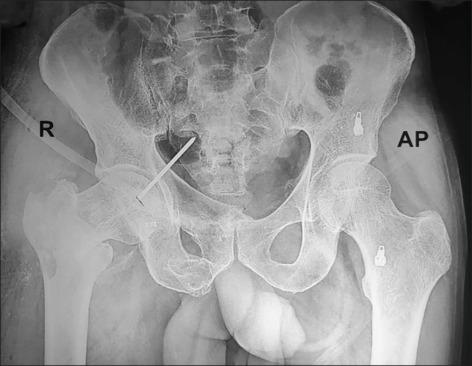

Retrieval of Broken Guidewire from the Hip Joint Protruding inside the Pelvic Cavity: A Rare Case Report.

Hardware breakage in the form of guide wire or drill bit is a devastating complication particularly if occurs around hip joint during cephalo-medullary nailing. It should be removed on urgent basis as it can migrate to the pelvic cavity and damages adjacent neuro-vascular bundle and visceral organ immediately as well joint arthritis later on. There are very few cases report available in the literature with retrieval techniques by using disc forceps, pituitary forceps, oversized reamers, arthrotomy with joint dislocation and through ilioinguinal approaches occasionally. We are presenting an interesting and rare case of broken guide wire inside hip joint protruding into the pelvic cavity which got retrieved through lower midline open laparotomy approach.

导丝或钻头形式的硬件断裂是一种极具破坏性的并发症,尤其是在股骨近端髓内钉固定过程中发生在髋关节周围时。应紧急取出,因为它可能迁移至盆腔,立即损伤相邻的神经血管束和内脏器官,以及随后导致关节关节炎。文献中很少有关于使用椎间盘钳、垂体钳、超大号扩孔钻、关节脱位切开术以及偶尔通过髂腹股沟入路进行取出技术的病例报告。我们现报告一例有趣且罕见的病例,髋关节内断裂的导丝突入盆腔,通过下腹部正中切口开腹手术取出。